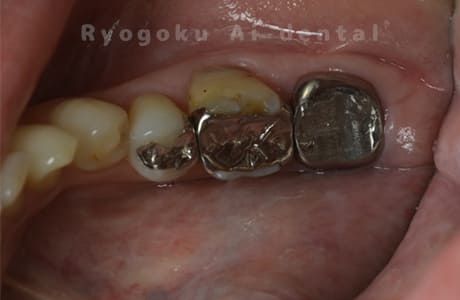

Case08

-

- 原因

- 歯根嚢胞、重度カリエス

- 治療内容

- 再植手術、クラウンレングスニング

- 治療費用

- ¥99,000

他院で根管治療を行ったが、なかなか治らず、抜歯を宣告されたとのことでご来院された患者様です。歯がかなり削られており、また、歯根の根尖部の病変が大きく、嚢胞化しているため、クラウンレングスニングと再植歯根端手術を同時に行いました。違和感もなくなり、大変満足されています。

<リスク・副作用>

外科手術のため、術後に出血、痛みや腫れ、違和感を伴います。口腔内の状態によっては適応できないことがあります。歯根端切除で治らなければ抜歯を検討しなくていけない場合もあります。